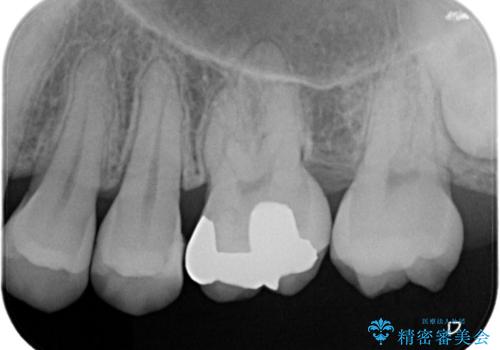

- 矯正終了後にメタルフリーの治療を希望された患者様です。

セラミックインレーにて修復治療を行なっております。

セラミックインレーのセット時にはラバーダムを用い防湿に気をつけて処置をしております。